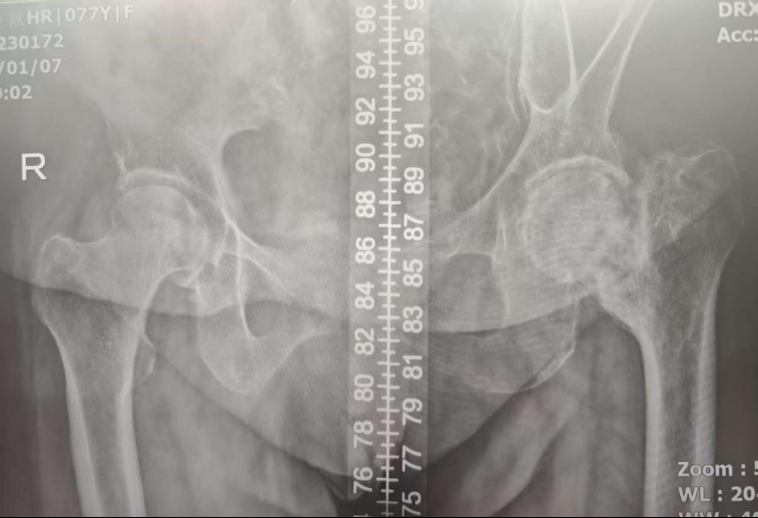

一年半前,李奶奶因摔伤导致左侧股骨颈骨折。由于她本身患有肝硬化晚期,身体状况极差,且血小板计数仅约30×10⁹/L(正常值120-300),远低于手术安全要求。因此,她只能接受保守治疗。然而,漫长的等待并未带来愈合,骨折处始终无法连接,并继发了股骨头坏死。持续的疼痛和无法行走,让李奶奶的生活质量急剧下降,身心承受着巨大痛苦,于是,家属带着李奶奶来到西安医学院第一附属医院骨科门诊。

“接诊后,我们发现患者的情况比较复杂,”骨科一病区孙甫副教授介绍,“影像学结果显示患者股骨头已坏死,保守治疗不能缓解,患者非常痛苦。但手术面临两大‘拦路虎’,一是严重的肝硬化导致的凝血功能障碍和极低的血小板计数,术中及术后发生大出血、感染、肝衰竭等风险概率大幅增加。二是患者高龄且长期卧床,身体机能衰退,手术耐受性差,术后并发症如深静脉血栓、肺部感染等发生风险也显著升高。这无疑是一场对医疗技术和团队协作的严峻考验,任何一个环节的疏忽都可能引发无法挽回的后果。”